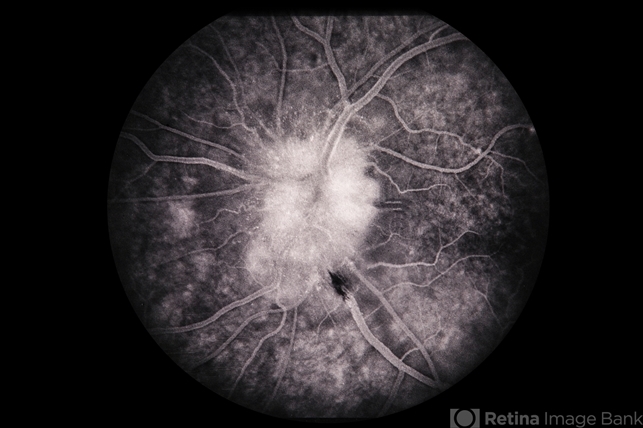

- Sarcoid PseudoMEWDS Papillitis

- sarcoidosis, multiple evanescent white dot syndrome (MEWDS), papillitis

- 34-year-old white male, sarcoid / pseudo-MEWDS / papillitis.